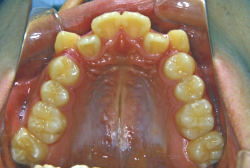

叢生(そうせい)

凸凹な歯並びのことを叢生といいます。矯正歯科に来院する患者様の主訴の中で、最も多いのが「配列の凸凹を真っ直ぐにしたい」というものです。歯の大きさと顎の大きさの調和がとれていないことが原因です。

凸凹を主体としたケースの場合、当院の平均治療期間は18ヶ月ですので、このケースは少し長めに経過しました。理由の一つは凸凹の程度がかなり重症だったと言うことですが、もう一つは、右下第2大臼歯が45度くらい前傾していたため、それを整直化させるために時間を要したと考えています。いずれにしても最終結果は大変よい状態と思います。

治療前は並びが乱れて見た目が悪いというのはもちろん問題ですが、歯科医学的に一番困るのは噛み合わせが悪いという点です。上下の犬歯(3番目の歯)は、上下的に離れた位置にあるため接触することができません。つまり歯としては存在していても、歯としては機能していないということです。